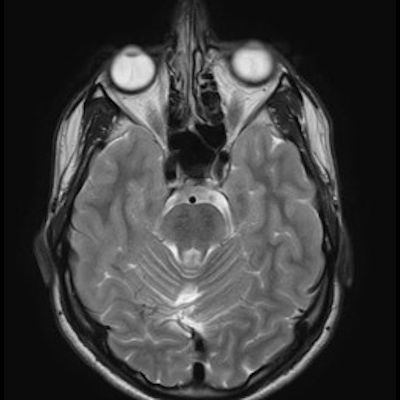

11 ay, Nöbet

Charlevoix-Saguenay Otozomal Resesif Spastik Ataksisi (ARSACS)

Charlevoix-Saguenay Otozomal Resesif Spastik Ataksisi ARSACS

ARSACS (Charlevoix-Saguenay otozomal resesif spastik ataksisi) Sendromu

Serebellar folya sinapsisi